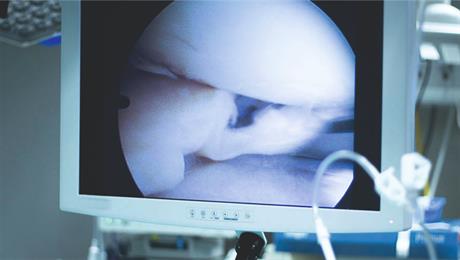

Liječenje bolesti zglobova artroskopskim zahvatom

Većina najčešćih ozljeda zglobova, puknuća, ruptura te degenerativnih promjena mogu se liječiti artroskopski